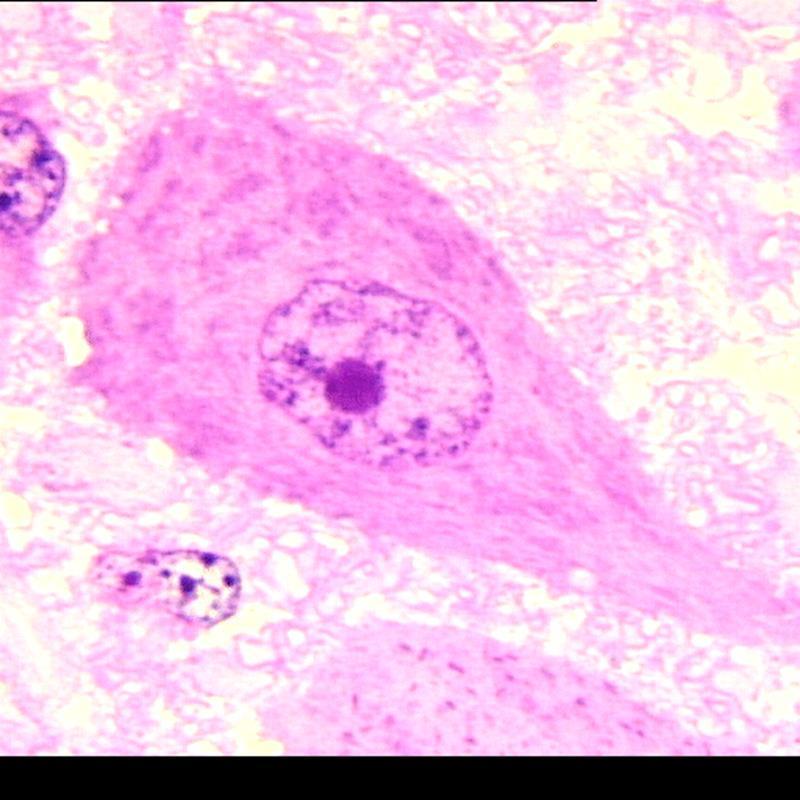

What are we looking at?

Neuron - see the cell body (parikaryon) containing nucleus, nucleolus, dendrites, and axon

What is this grainy basophilic substance?

Nissl substance - dark due to presence of RER and ribosomes